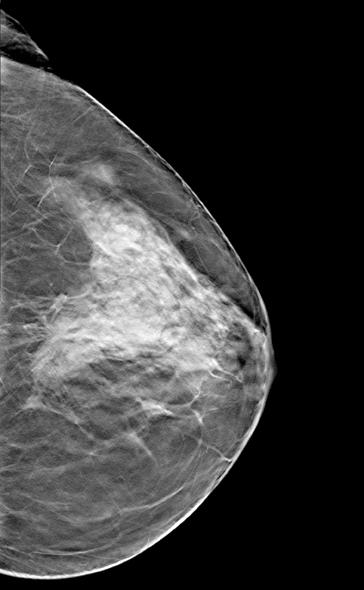

Despite decades of progress in breast imaging, one challenge continues to test even the most skilled radiologists ...

For patients with advanced breast cancer, positron emission tomography (PET) and magnetic resonance (MR) imaging can improve quality of life and survival by providing physicians with information on the effectiveness of chemotherapy prior to surgery, say researchers presenting at the 2013 Annual Meeting of the Society of Nuclear Medicine and Molecular Imaging.